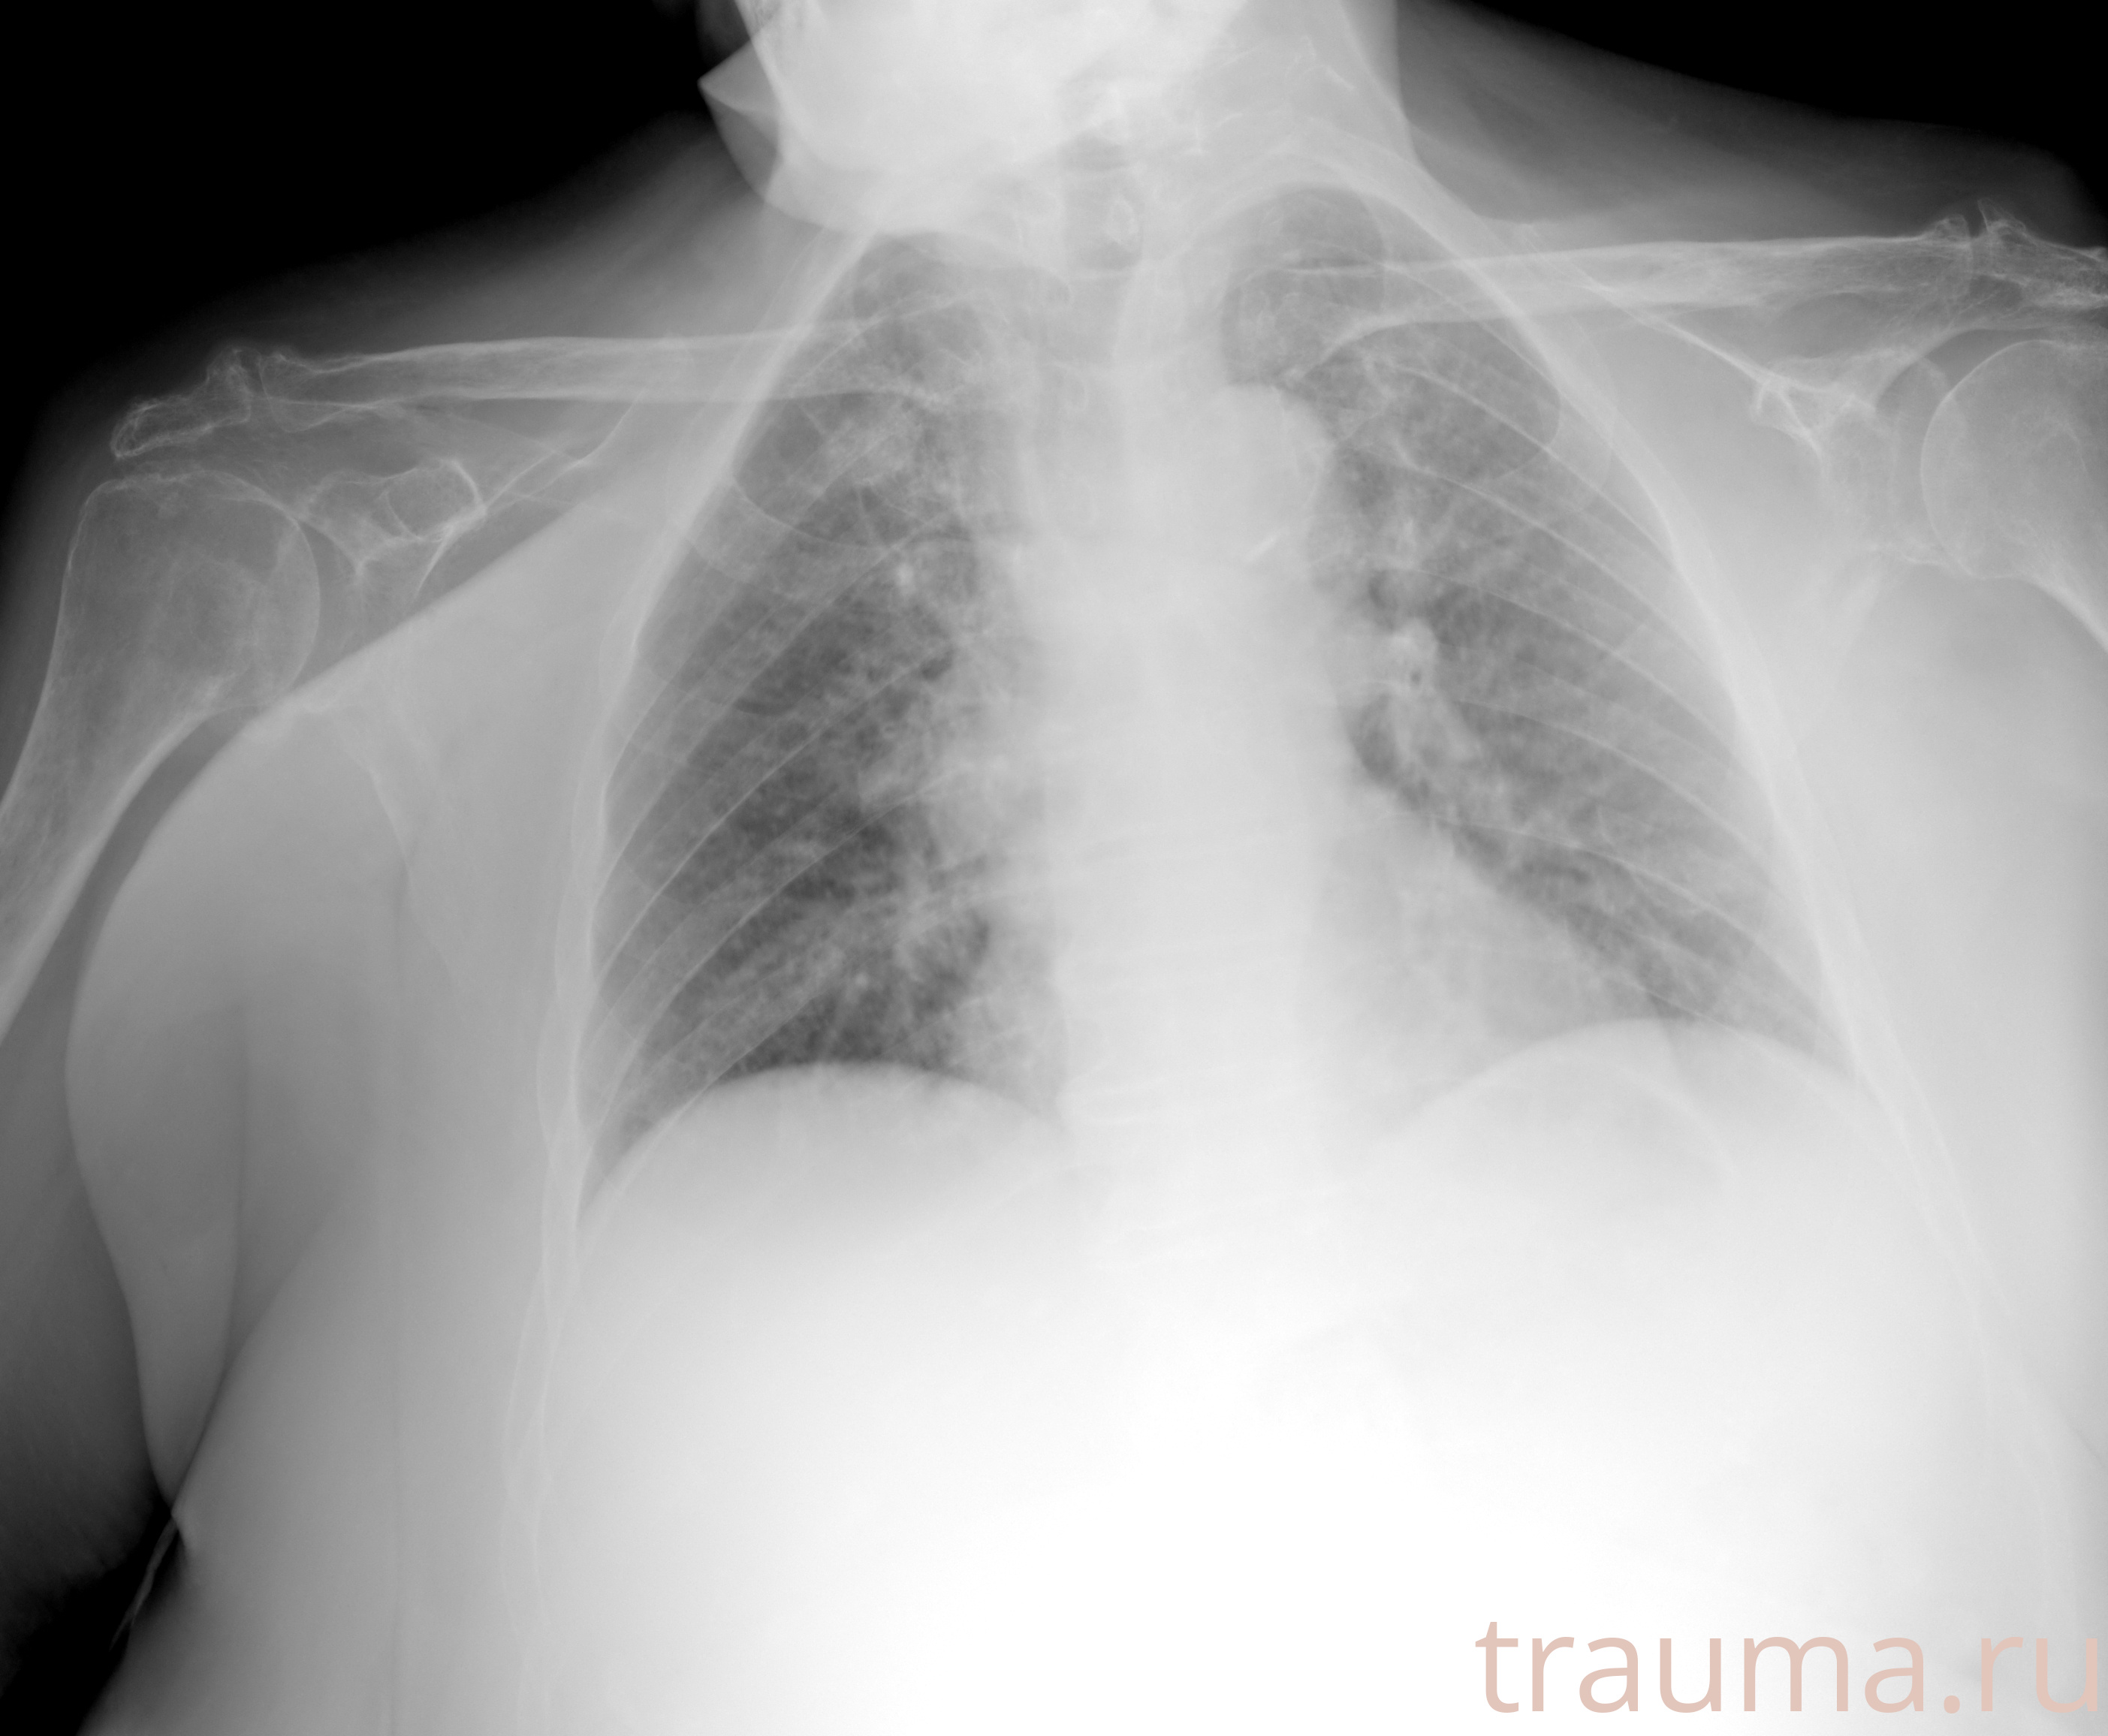

Рентгенограммы

Рентген на дому: по вашему адресу приезжает врач-рентгенолог, травматолог-ортопед с мобильным рентгеновским аппаратом, проводит диагностику травмы или заболевания, делает необходимые рентгенограммы, дает рекомендации по дальнейшему лечению. Получить качественные снимки в домашних условиях возможно благодаря уникальной методике, разработанной МосРентген Центром для института  Склифосовского

при переломе шейки бедра и пневмонии от компании МосРентген Центр - партнера Института имени Склифосовского